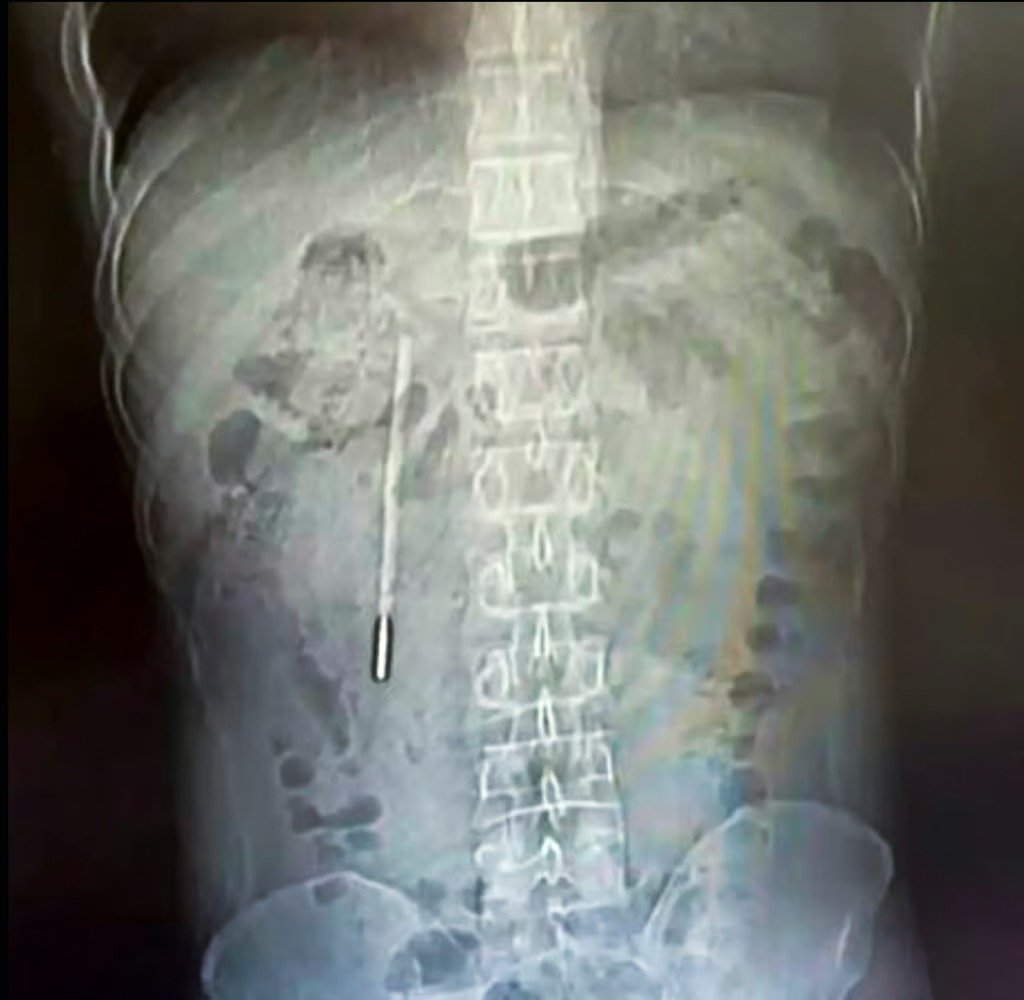

רופאים בסין נדהמו לגלות כי כאבי הבטן מהם סבל מטופל שהגיע לבית החולים, נגרמו כתוצאה ממדחום כספית ששהה במערכת העיכול שלו במשך 20 שנה. המטופל, המכונה וואנג, הודה לאחר הניתוח כי בלע את המכשיר בטעות כשהיה בן 12, אך בחר להסתיר את הדבר מהוריו מחשש לתגובתם.

הבדיקות הרפואיות העלו כי המדחום ממוקם בתריסריון, כאשר קצהו לוחץ ישירות על דופן המעי. מיקום זה העמיד את וואנג בסיכון גבוה לניקוב דופן המעי ולדימום פנימי חמור. בשל העובדה שהמדחום שכב סמוך לצינורות המרה במשך תקופה כה ממושכת, נדרשו המנתחים לדיוק מרבי כדי למנוע דליפת כספית רעילה או פגיעה ברקמות פנימיות.